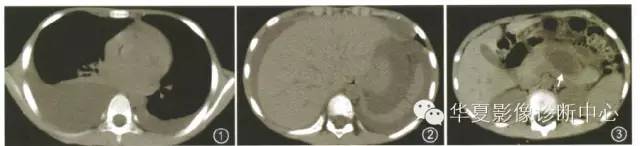

CT检查(图1~3):双侧胸腔及腹腔积液;胰腺假性囊肿。予禁食、施他宁静脉点滴维持,静脉营养及维持水电解质平衡等治疗。经上述治疗2个月后患者症状减轻,胸水、血及尿液淀粉酶逐步恢复正常。

图1~3例1。CT示双侧胸腔积液(图1),肝周带状低密度影(图2),胰腺体部见囊状低密度灶(图3,箭)